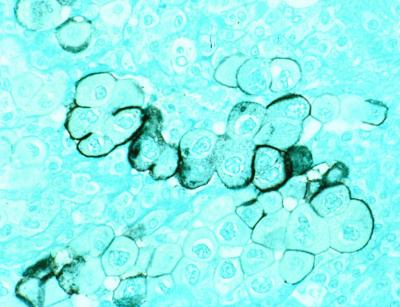

The study of blood samples from more than 800 European adults, published online Sept. 18 in the journal Gut , found that high antibody levels for one of the more infectious periodontal bacterium strains of Porphyromonas gingivalis were associated with a two-fold risk for pancreatic cancer. Meanwhile, study subjects with high levels of antibodies for some kinds of harmless "commensal" oral bacteria were associated with a 45-percent lower risk of pancreatic cancer.

Several researchers, including Michaud, have found previous links between periodontal disease and pancreatic cancer. The Gut paper is the first study to test whether antibodies for oral bacteria are indicators of pancreatic cancer risk and the first study to associate the immune response to commensal bacteria with pancreatic cancer risk. The physiological mechanism linking oral bacteria and pancreatic cancer remains unknown, but the study strengthens the suggestion that there is one.